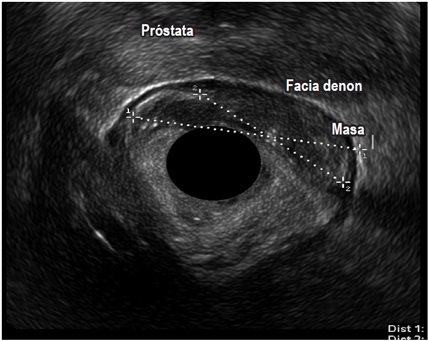

Por otro lado, en el grupo masculino con estudio por incontinencia, el diagnóstico en todos fue cambios por atrofia del aparato esfinteriano, que pudo verse en cualquiera de las localizaciones del canal anal y que se evidenció como engrosamiento de los músculos en general y cambios difusos de la ecogenicidad de los mismos, sin posibilidad de determinar el borde que los delimita. Se encontró fístula perianal en 16 pacientes (11,8%); la principal forma de presentación de las fístulas fue transesfintérica (37,5%), seguida por las interesfintéricas y anovaginales (figuras 3 y 4). Doce pacientes presentaron absceso perianal (8,8%); de estos, el 83% correspondió a abscesos submucosos o isquiorrectales (figura 5).

Los demás diagnósticos finales se presentan en la tabla 4. Es de resaltar que se pudo determinar en el grupo diagnosticado como neoplasia benigna de recto, la posibilidad de resección endoscópica en lesiones que tenían planeadas cirugías más invasivas (figura 6 y 7), así como la posibilidad de determinar la recuperación del aparato esfinteriano en 3 pacientes en seguimiento por cáncer de canal anal después de manejo por parte de oncología. En 2 pacientes de los diagnosticados con neoplasia maligna de recto se identificó lesión menor a T2 y N0 según las clasificación de TNM (figura 8), considerándose lesiones tempranas; en el otro 88,8% se encontraron lesiones avanzadas (figura 9 y 10). También se anota que, dentro de la categoría otros, están con orden de frecuencia de mayor a menor endometriosis o endometrioma, enterocele, fisura anal, várices rectales y un caso de cáncer de colon sigmoides.

De igual forma, la importante frecuencia de indicación en pacientes con neoplasia maligna rectal confirmada habla de la aceptación a nivel nacional y regional que se le está dando a este diagnóstico por parte de grupos interdisciplinarios de oncología, donde la endosonografía juega un papel fundamental a la hora de complementar otras ayudas diagnósticas para estadificación locorregional y planeamiento adecuado de la terapia (4, 9, 19, 20, 21, 22).